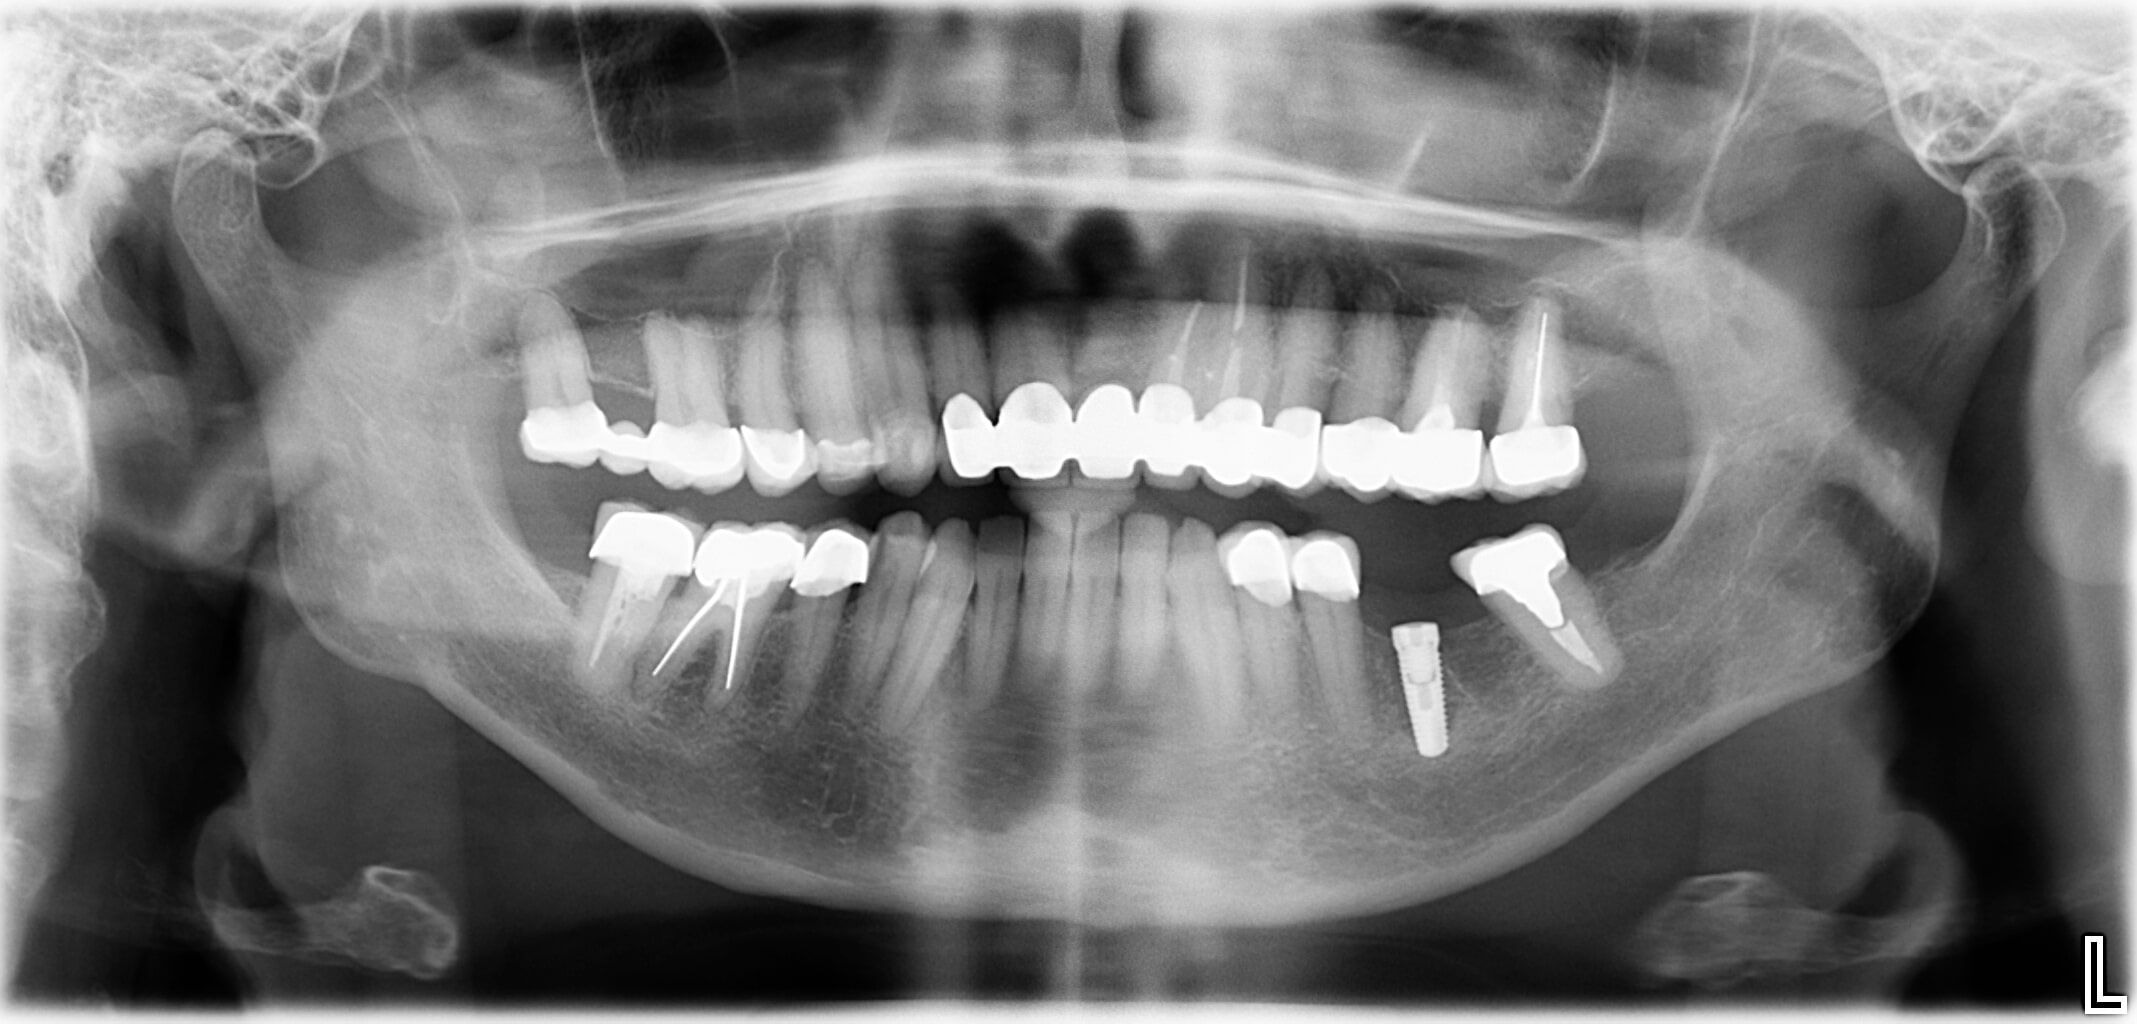

Der Behandlungsablauf startet mit einer eingehenden Diagnostik, das heißt, die Spezialisten für Oralchirurgie und Implantologie in der Zahnarztpraxis Dr. Kaiser & Kollegen beurteilen mittels Röntgendiagnostik und digitaler Volumentomografie den Zustand des Kieferknochens. Dank dreidimensionaler Bildgebung kann festgestellt werden, wo ein Sinuslift notwendig ist.

Ist die bildgebende Diagnostik abgeschlossen, kann der behandelnde Zahnarzt beurteilen, wie viel Knochenangebot vorhanden ist und wie viel Knochenersatzmaterial notwendig ist, um einen sicheren Halt des geplanten Implantats zu erreichen. Davon abhängig wird entweder der interne Sinuslift, der externe Sinuslift oder das Ballonverfahren als Operationsvariante festgelegt.